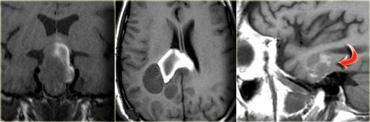

Việc phân biệt trong trục và ngoài trục thường khá rõ ràng, nhưng đôi khi có thể rất khó khăn và cần chụp hình ảnh trên nhiều mặt phẳng.

Khối u trong trường hợp bên trái ban đầu được nghĩ là u màng não liềm não (falcine meningioma), tức là ngoài trục, và được chỉ định phẫu thuật.

Tổn thương này có hình ảnh rất giống u màng não: các u này có thể giảm tín hiệu trên T2W do chất nền xơ-collagen hoặc vôi hóa, và thường gây phù nề phản ứng ở chất trắng não lân cận.

Tuy nhiên, có chất xám ở phía trước-trong và sau-trong của tổn thương (mũi tên đỏ).

Điều này cho thấy tổn thương nằm trong trục.

Nếu tổn thương là ngoài trục, chất xám đáng lẽ phải bị đẩy lệch.

Trường hợp này được xác định là di căn u hắc tố (melanoma).